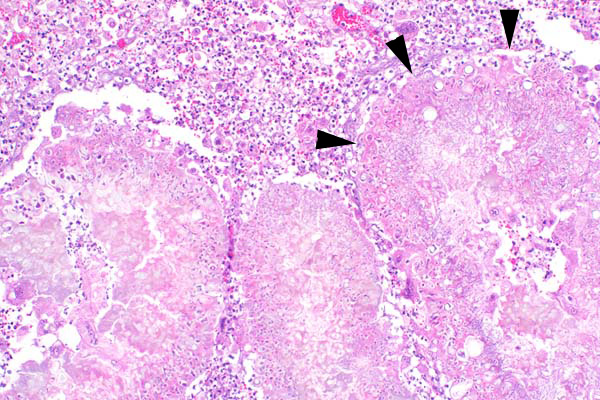

Large aggregates of fungal hyphae and conidia (arrowheads) are surrounded by macrophages, degenerate neutrophils and multinucleated giant cells.